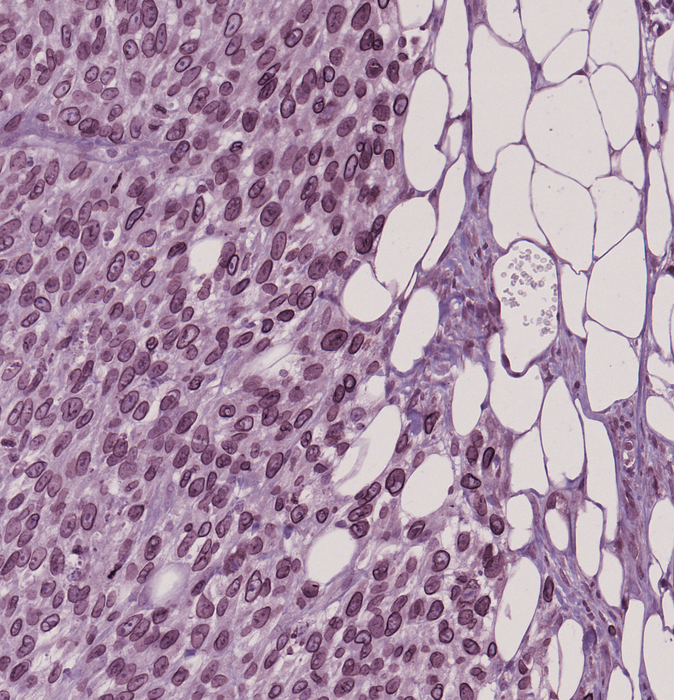

Imaging conducted after the migration experiments showed that the aggressive cells were able to move through the pores more effectively than the less-aggressive ones by forming bulges at the edge of their nucleus called ‘blebs’. Genetic analyses of the melanoma cells revealed that the aggressive cells that formed the blebs contained higher levels of the LAP1 protein, which sits within the membrane that surrounds the nucleus (called the nuclear envelope).

The team also observed the same pattern of LAP1 expression in melanoma samples from patients. LAP1 levels were higher in tissue samples taken from sites of metastasis in melanoma patients compared to the levels found in primary tumours. The patients that had high levels of LAP1 in the cells around the edge of the primary tumour had more aggressive cancer and poorer outcomes, suggesting that the protein could be used to identify subpopulations of melanoma patients that may be at higher risk of aggressive disease.